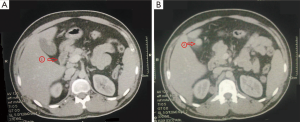

An abdominal computed tomography (CT) scan has found many circumferential thickening of ileal loops with the presence of peri-intestinal, peri-renal and inguinal lumph nodes, associated with a nodular lesion in the anterior wall of the gallbladder (Figure 4).